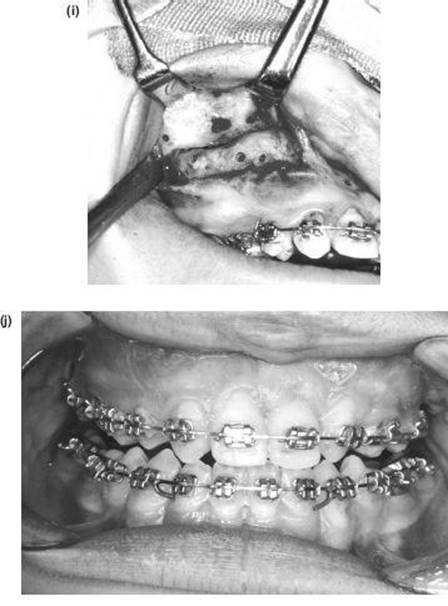

The Inverted L Osteotomy

Indications

This operation is valuable when there is a need to increase both the ramus height and body length at the same time, especially when the sagittal split osteotomy is not possible. Such cases are usually gross congenital mandibular hypoplasia or, occasionally, acquired hypoplasia following condylar fractures or when previous surgery has disturbed the bony anatomy. The operation differs in concept from the sagittal split procedure in that a bone graft is inserted to make up the deficiency.

Technique

1. The surgical approach is exactly the same as for the extraoral subsigmoid osteotomy (steps 1-6 and see Figure 9.4) except that the bone cut is made from the anterior border of the ascending ramus, passing distally, to behind the estimated position of the lingula then downwards to the lower border anterior to the angle, i.e. to the antegonial notch (Figure 9.7a).

2. With bilateral deformities the approach is repeated on the opposite side.

3. The mandible is then temporarily fixed into occlusion. Where the maxilla is normal this presents no problems. However, if there is a deformity of the maxilla this must be corrected before the inverted L and fixed with bone plates.

Mobilising the small mandible into the desired anterior position can be difficult and is facilitated by drilling a hole bilaterally in the lower border of the mandible just anterior to the osteotomy cut and passing a 0.5 mm traction wire to be attached to heavy forceps. When anterior traction is applied, explore the deep tissues medial to the mandible with a finger to find any restraining bands of periosteum, muscle or ligament. These must be vigorously divided with the finger to ensure stability.

4. With the proximal condylar fragment confirmed to be in the fossa, the gap created can be measured, and a template formed with sterile paper or card.

Figure 9.7 (a), (b)

5. An interpositional graft is now obtained. The ideal source is cortico-cancellous bone from the iliac crest. A solid cancellous graft can be used but the incorporation of one cortex provides reassuring stability. Some surgeons use split rib for the gap. Two miniature bone plates provide excellent rigidity and form (Figure 9.7b).

6. A vacuum drain is inserted and the wound is closed in layers.

7. The intermaxillary fixation is released and the pack removed.

Note: Any mandible which requires lengthening with an inverted L osteotomy also requires an augmentation genioplasty.